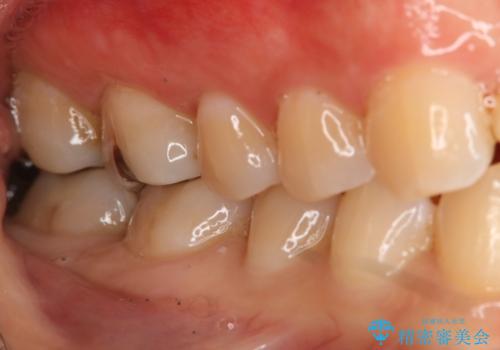

奥歯を綺麗にしたい

- 右下6・7番の咬合面に詰められた保険材料が劣化していたので、審美性・切削量を考慮しセラミックインレー治療を選択しました。

劣化した保険材料・虫歯を全て除去した上で形成しています。